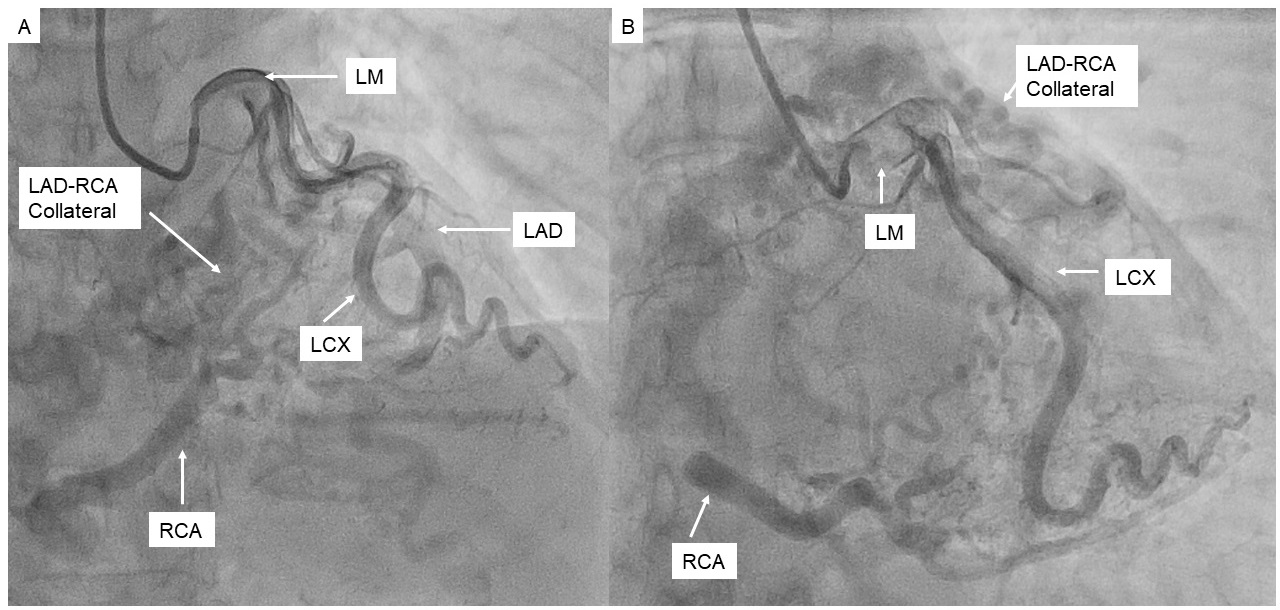

Selective left coronary angiography showed an ectatic left main artery and tortuous collaterals from the proximal left anterior descending (LAD) artery to a severely ectatic right RCA. The LAD was also severely ectatic and filled late. Retrograde filling of the pulmonary artery from the RCA was visualized (Figure 1, Video 1). We were unable to engage the RCA selectively with multiple diagnostic catheters. Ascending aortography confirmed absence of RCA ostium from the aorta and suggested the diagnosis of anomalous right coronary artery from pulmonary artery (ARCAPA) (Figure 2, Video 2). CT angiography confirmed ARCAPA with large left-to-right collaterals from LAD to RCA (Figures 3-5). There were no other congenital heart anomalies. Echocardiography showed normal biventricular function and normal chamber sizes. A myocardial perfusion Single Photon Emission Computed Tomography (SPECT) study showed a moderate intensity, medium-sized, partially reversible defect in the RCA distribution. The patient was referred to cardiothoracic surgery for consideration of reimplantation of the RCA to the aorta. However, due to her asymptomatic status at baseline, the decision was made to pursue initial conservative management.